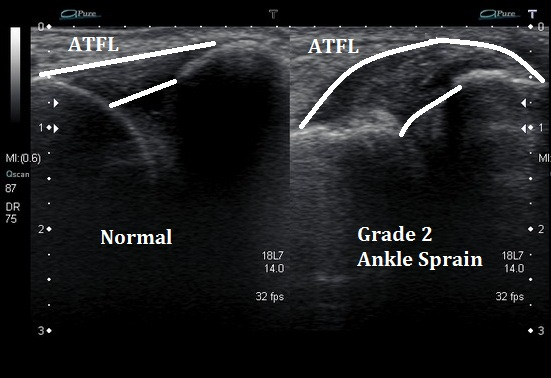

Le chiropracteur procède à des tests orthopédiques spécifiques pour évaluer la mobilité et identifier les ligaments touchés. En fonction des résultats, il pourra également vous prescrire une imagerie médicale, telle qu’une échographie et/ou une radiographie, afin d’identifier avec précision les structures en souffrance. Cela permet de visualiser les éventuels dommages ligamentaires, tendineux ou osseux, et d’ajuster le traitement en fonction de la gravité de la blessure.

• Échographie : Permet de visualiser les lésions ligamentaires et tendineuses.

Classification : Les grades des entorses

L’entorse de la cheville est classée selon trois grades, en fonction de la sévérité de la blessure et des structures ligamentaires atteintes :

• Grade 1 : Élongation ou déchirure minime des fibres ligamentaires. La douleur et l’enflure sont modérées, et la stabilité articulaire est conservée.

• Grade 2 : Déchirure partielle du ligament avec douleur, enflure importante et instabilité articulaire modérée.

• Grade 3 : Rupture complète du ligament. L’instabilité est marquée, avec une douleur et une enflure très importantes.